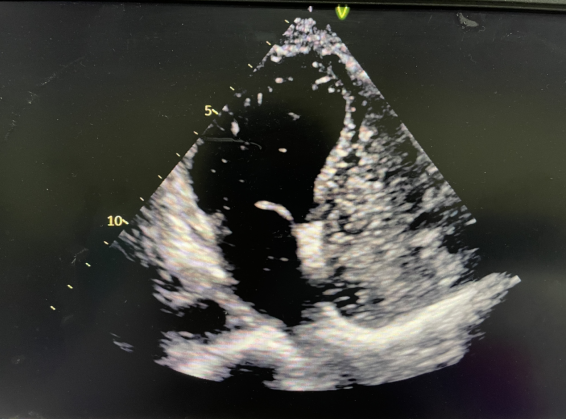

超声诊断中心主任尹安平带领葛乃红医师为陈女士共同完成了“右心声学造影”检查。检查结果印证了沈斌主任的判断,结果显示:患者在Valsalva运动后,左心内可见3-5个微气泡。在超声诊断上属于卵圆孔未闭,尽管分流很少,但这就是她偏头痛的原因。

右心声学造影在卵圆孔未闭的诊断中确实具有独特的优势。卵圆孔未闭发生率其实很高,在人群中卵圆孔发生率可以达到约20%-25%,也就是说,10个人中会有2个人患有卵圆孔未闭,卵圆孔未闭没有特殊症状一般无需特殊治疗。

少数卵圆孔未闭的患者会合并偏头疼,甚至会发生脑卒中。如果反复发生偏头疼又找不到其它原因,建议做“右心声学造影”排除是否“卵圆孔未闭”导致。